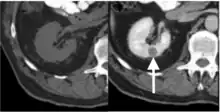

Currently, cross-sectional imaging with computed tomography (CT) and magnetic resonance imaging (MRI) is known as the best option for diagnosing papillary renal tumors.[29]

Computed tomography (CT)

Contrast-enhanced computed tomography (CT) is most commonly used to identify the subtypes of RCC. PRCC can be differentiated from other types of RCC due to its distinguishing features, displaying a small hypovascular renal tumor on T2 weighted images.[7] Typically, PRCC tends to appear homogeneous while clear cell RCC is likely to be in a heterogeneous form when the tumor is less than 3 cm in diameter.[30] Comparatively, in cases of tumors larger than 3 cm in diameter, PRCC is generally heterogeneous with areas of necrosis and hemorrhage compared to chromophobe RCC.[8][31] Solid, small PRCC tumors (<3 cm in diameter) are more easily viewed on nephrographic, excretory phase images rather than on unenhanced, corticomedullary phase images.[8]